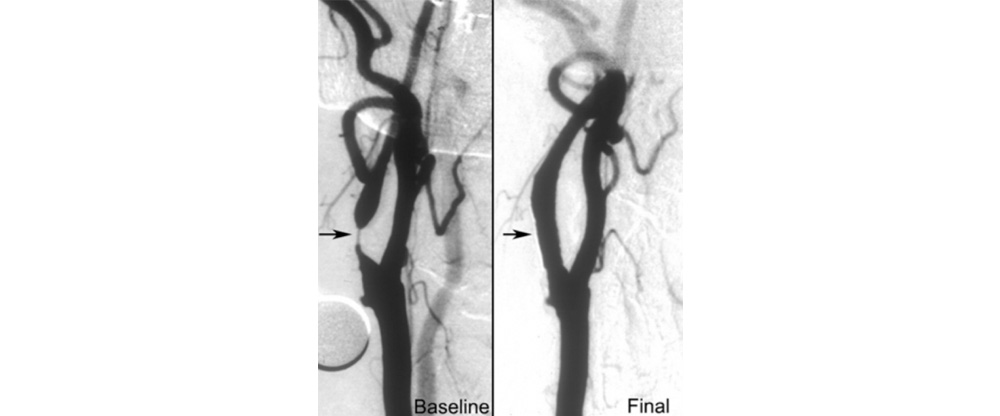

This can be treated with medical management, surgery or stenting based on the clinical scenario. If the narrowing is > 50-60% the carotid artery can be treated with stenting which is a minimally invasive procedure.